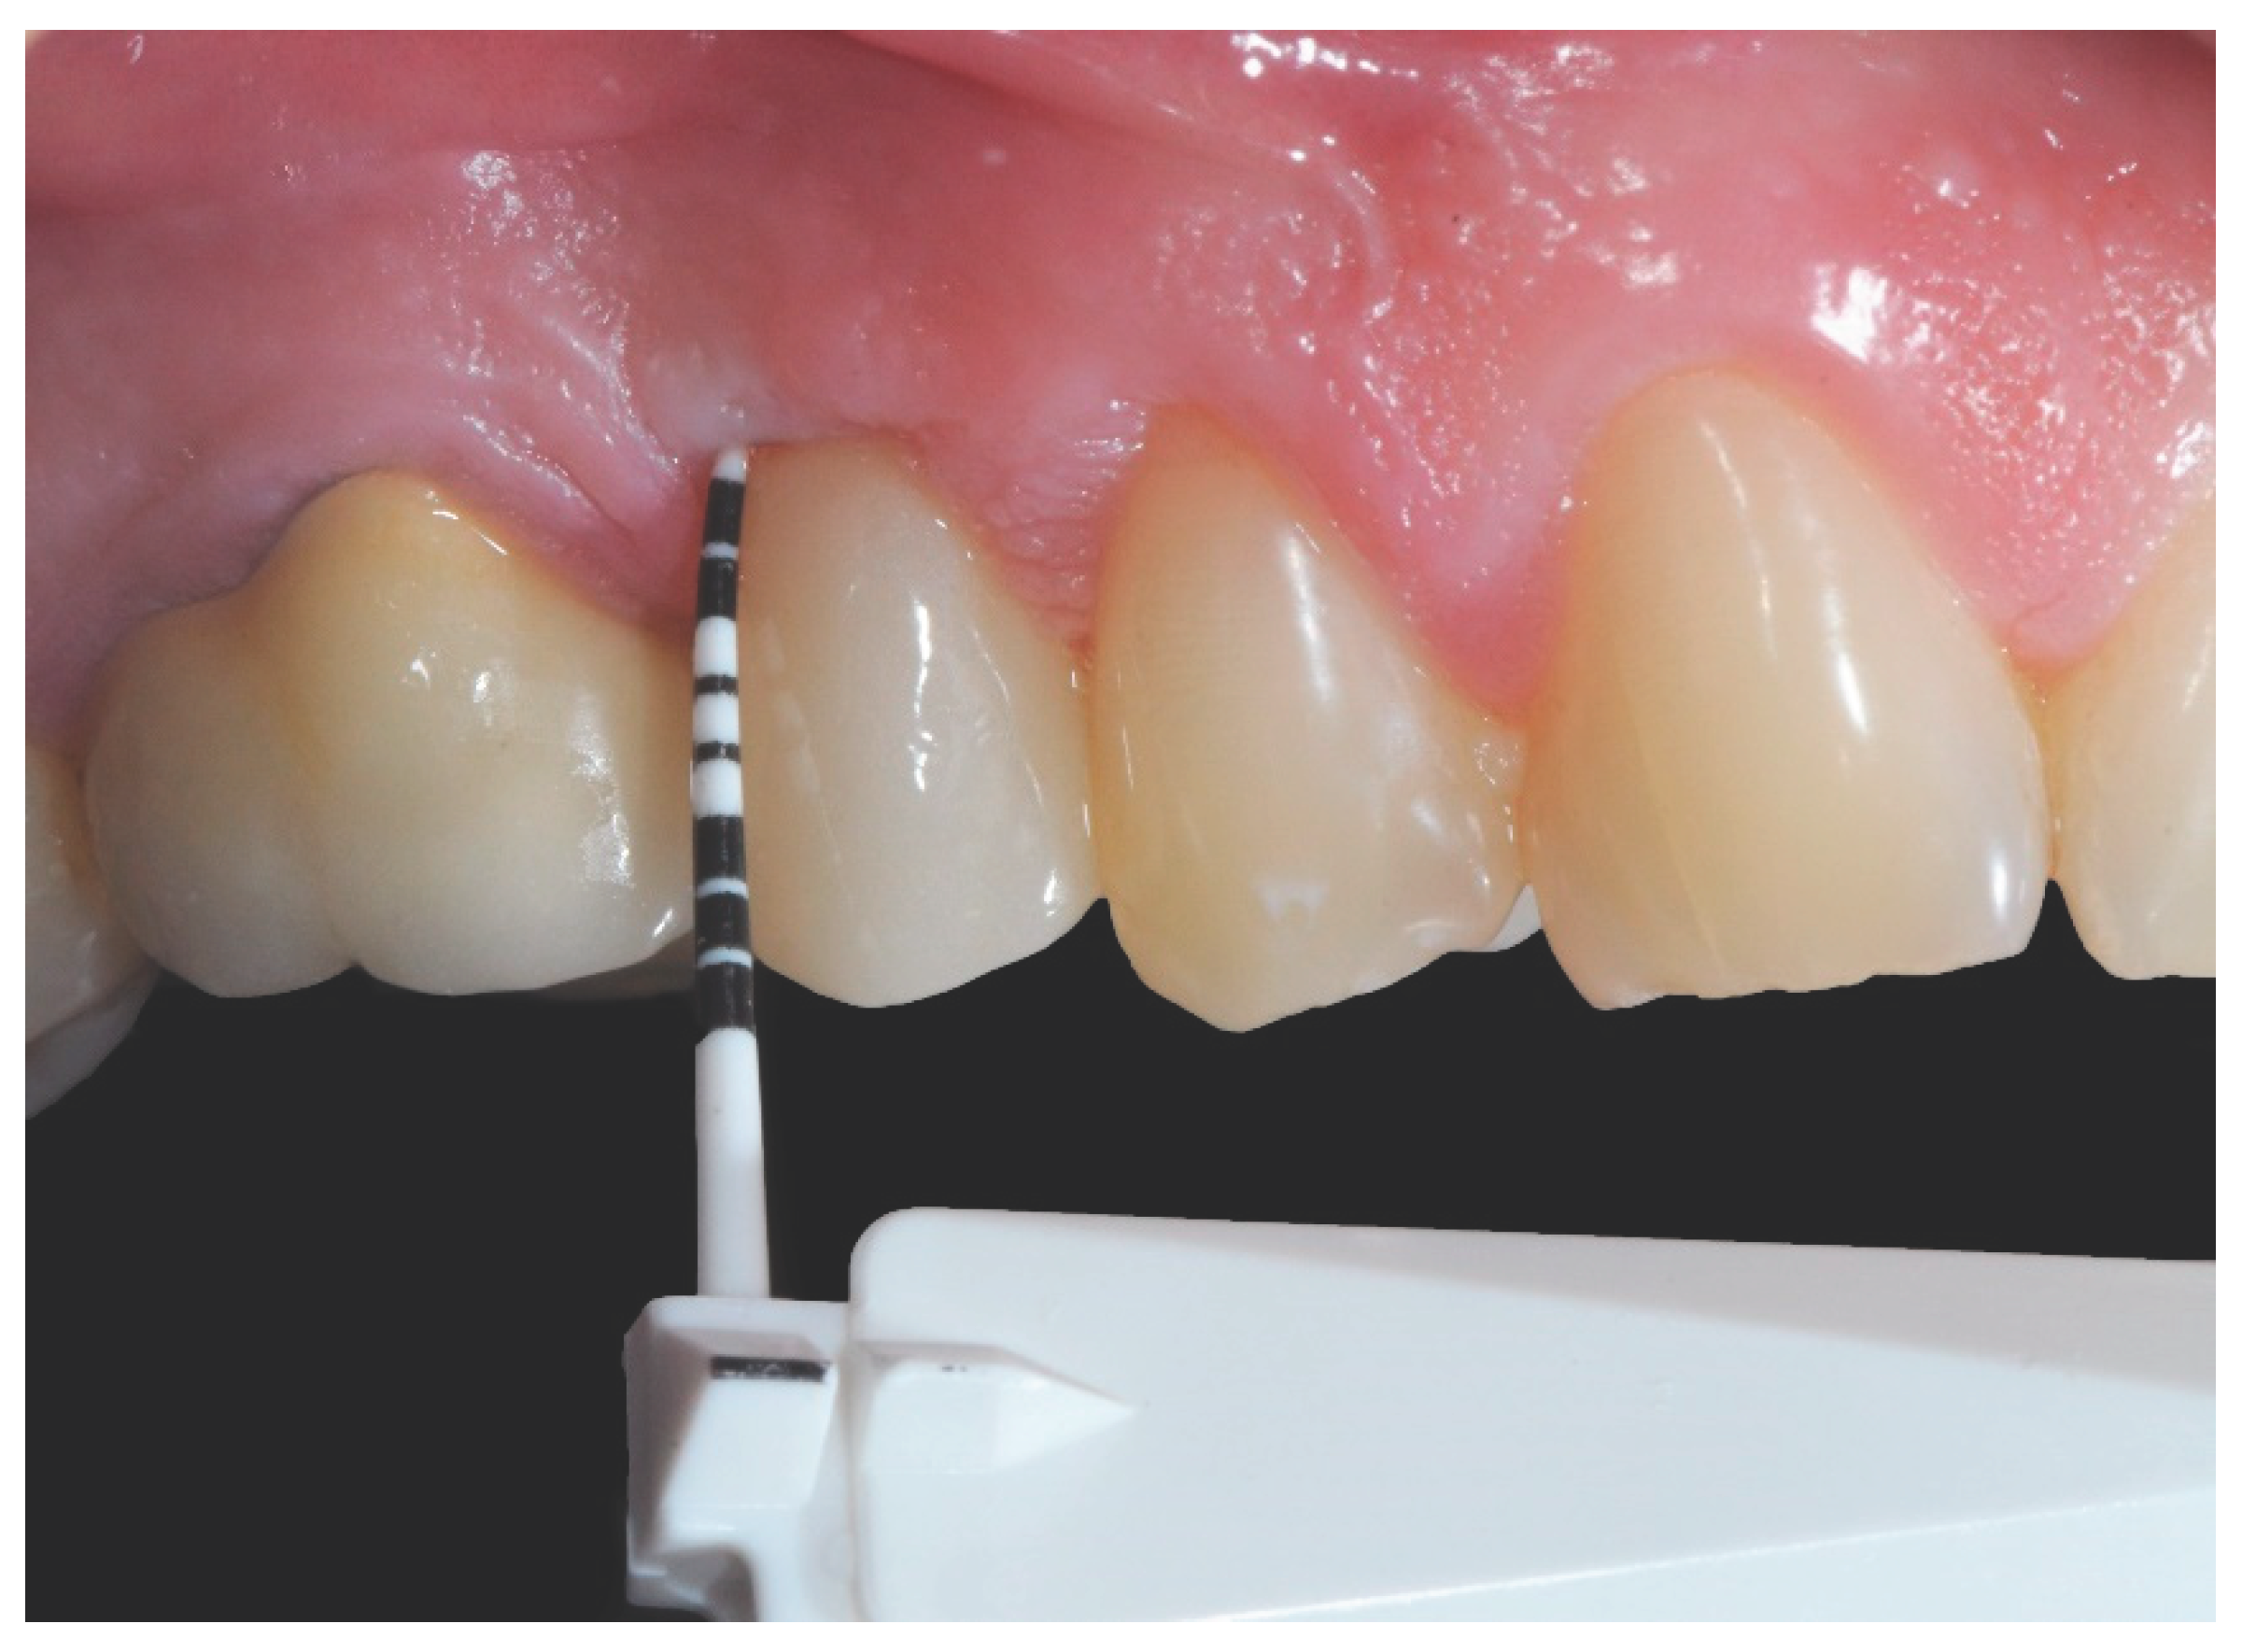

2.5. Clinical Evaluations

| Clinical Parameter |

Control Group** | Test Group* | TEST VS Control | |||||

|---|---|---|---|---|---|---|---|---|

| 6 months | 1 year | 1 year VS 6 months |

6 months | 1 year | 1 year VS 6 months |

6 months | 1 year | |

| PPD (mm) (CI 95%) |

3.18 (2.76; 3.60) |

3.04 (2.64; 3.45) |

0.04 (-0.72; 0.45) p=0.641 |

2.33 (2.03; 2.63) |

2.38 (2.13; 2.62) |

0.04 (-0.35; 0.43) p=0.834 |

-0.85 (-1.36; -0.33) p=0.001 |

-0.67 (-1.14; -0.19) p=0.006 |

| BOP (%) (CI 95%) |

55.56 (43.90; 70.31) |

43.06 (33.54; 55.27) |

0.78 (0.56; 1.08) [p=0.134] |

36.11 (24.51; 53.21) |

50.00 (36.40; 68.68) |

1.38 (0.86; 2.23) [p=0.180] |

0.65 (0.41; 1.02) [p=0.0627] |

1.16 (0.78; 1.74) [p=0.4681] |

| PI(%) (CI 95%) |

12.50 (4.90; 31.89) |

19.44 ( 10.54; 35.86) |

1.56 (0.49; 4.89) [p=0.44979] |

11.11 (5.03; 24.53) |

33.33 (21.00; 52.91) |

3.00 (1.33; 6.79) [p=0.00837] |

0.89 (0.26; 3.03) [p=0.851] |

1.71 (0.80; 3.69) [p=0.168] |